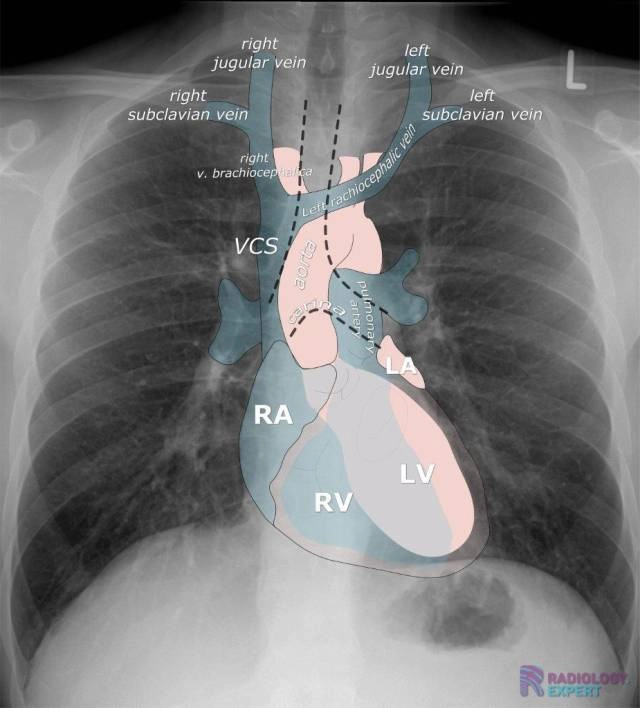

Giải phẫu X quang Phổi cơ bản

16/03/2026